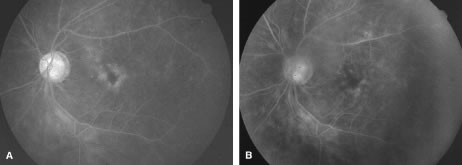

The ARN patient typically presents with progressive visual blurring in one or both eyes occurring over several weeks. These patients often are initially treated with corticosteroids, antitoxoplasmosis drugs, and other medications before arriving at the correct diagnosis. Examination reveals a prominent anterior uveitis that may be granulomatous or nongranulomatous (Fig. 1). Inflammatory signs may be prominent and cause severe pain (Fig. 2). The uveitis may be diffuse and so severe that it causes proptosis. These signs, and the diffuse vitreitis that makes the view of the retina difficult, may contribute to the high degree of delayed and/or misdiagnosis that occurs in the early stages of the disease. Significant vitreous cellular infiltration is seen in the presence of retinitis that is manifest by opacification of the retina, often most prominently in the periphery. Posterior pole involvement may include retinitis, as well as inflammation of the optic nerve head. Optic neuropathy might be the first sign of ARN with subsequent development of other retinal manifestations.8 Ultrasonography and computed tomography (CT) might be helpful in cases of ARN associated with optic nerve edema revealing enlargement of the optic nerve sheath.9 Even in ARN patients who are not immunocompromised and who have no clinical evidence of encephalitis, magnetic resonance imaging of selected cases has shown lesions of the lateral geniculate, optic tracts, and chiasma, which suggests that the virus spreads through the central nervous system (CNS) by axoplasmic transport from the retinal ganglion cells.10 A secondary retinal vasculitis is common, often accompanied by a mild number of retinal hemorrhages. Days to weeks after onset of the infection, the discrete peripheral lesions typically coalesce into a white or yellow ring of infected retina, and the associated vasculature is obliterated (Fig. 3). Necrotic retina desquamates into the vitreous resulting in vitreous sheets.3,6 Eventually, most untreated eyes can be expected to develop retinal detachment resulting from development of multiple full-thickness retinal breaks accompanied by traction or exudation.11 Giant retinal pigment epithelial tears have also been reported.12